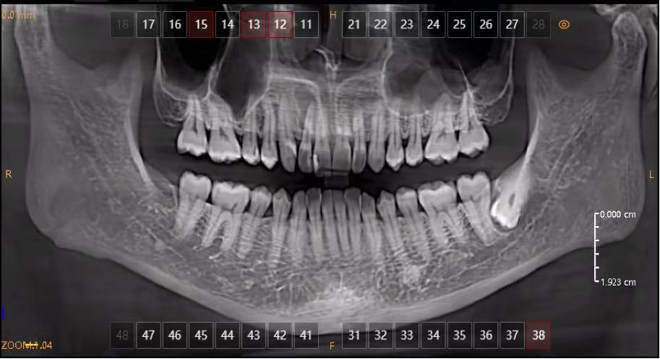

Panoramic radiograph reveals a large radiolucent lesion at the apex of #12